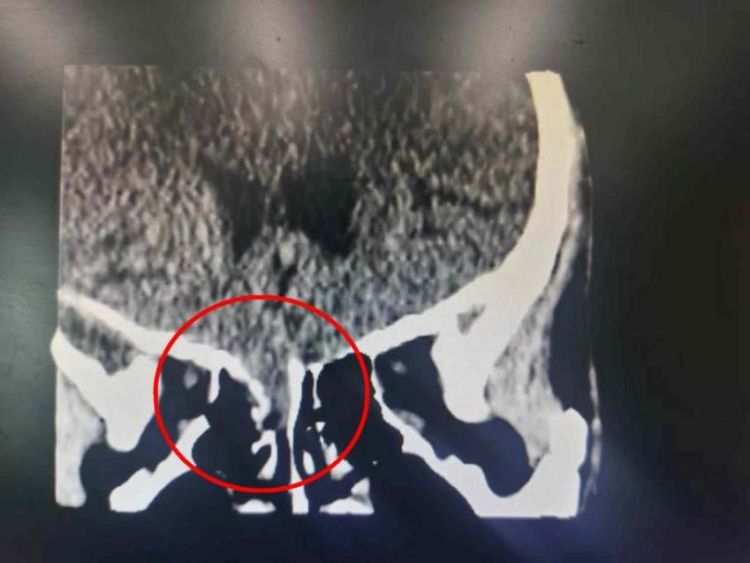

结果不查不知道,一查吓一跳,赵先生的前颅底骨折,而且额底的部分脑组织透过骨折缺失的地方挤入了鼻腔,并伴有脑脊液漏!

疝出的部分脑组织影像

说得通俗些,赵先生的这次车祸把“脑子”都摔出来了!